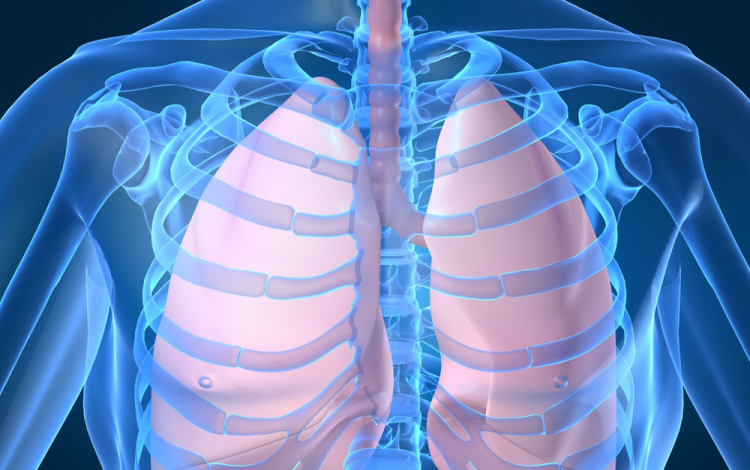

Húszan várnak tüdőátültetésre Magyarországon

Húszan várnak tüdő-transzplantációra az országban, tavaly 12 magyar betegen hajtottak végre ilyen szervátültetést külföldön

- mondta Kásler Miklós, az Országos Onkológiai Intézet főigazgatója vasárnap az M1 aktuális csatorna esti műsorában. A főigazgató ezt azzal kapcsolatban közölte, hogy még idén elvégezhetik az első tüdőátültetést Magyarországon.

Magyarországról tavaly 37 tüdőt szállítottak Bécsbe átültetési céllal; ha nálunk is elérhetővé válik a műtét, akkor várhatóan a környező országokból is Budapestre érkezik majd a betegek egy része Bécs helyett - mondta a főigazgató.